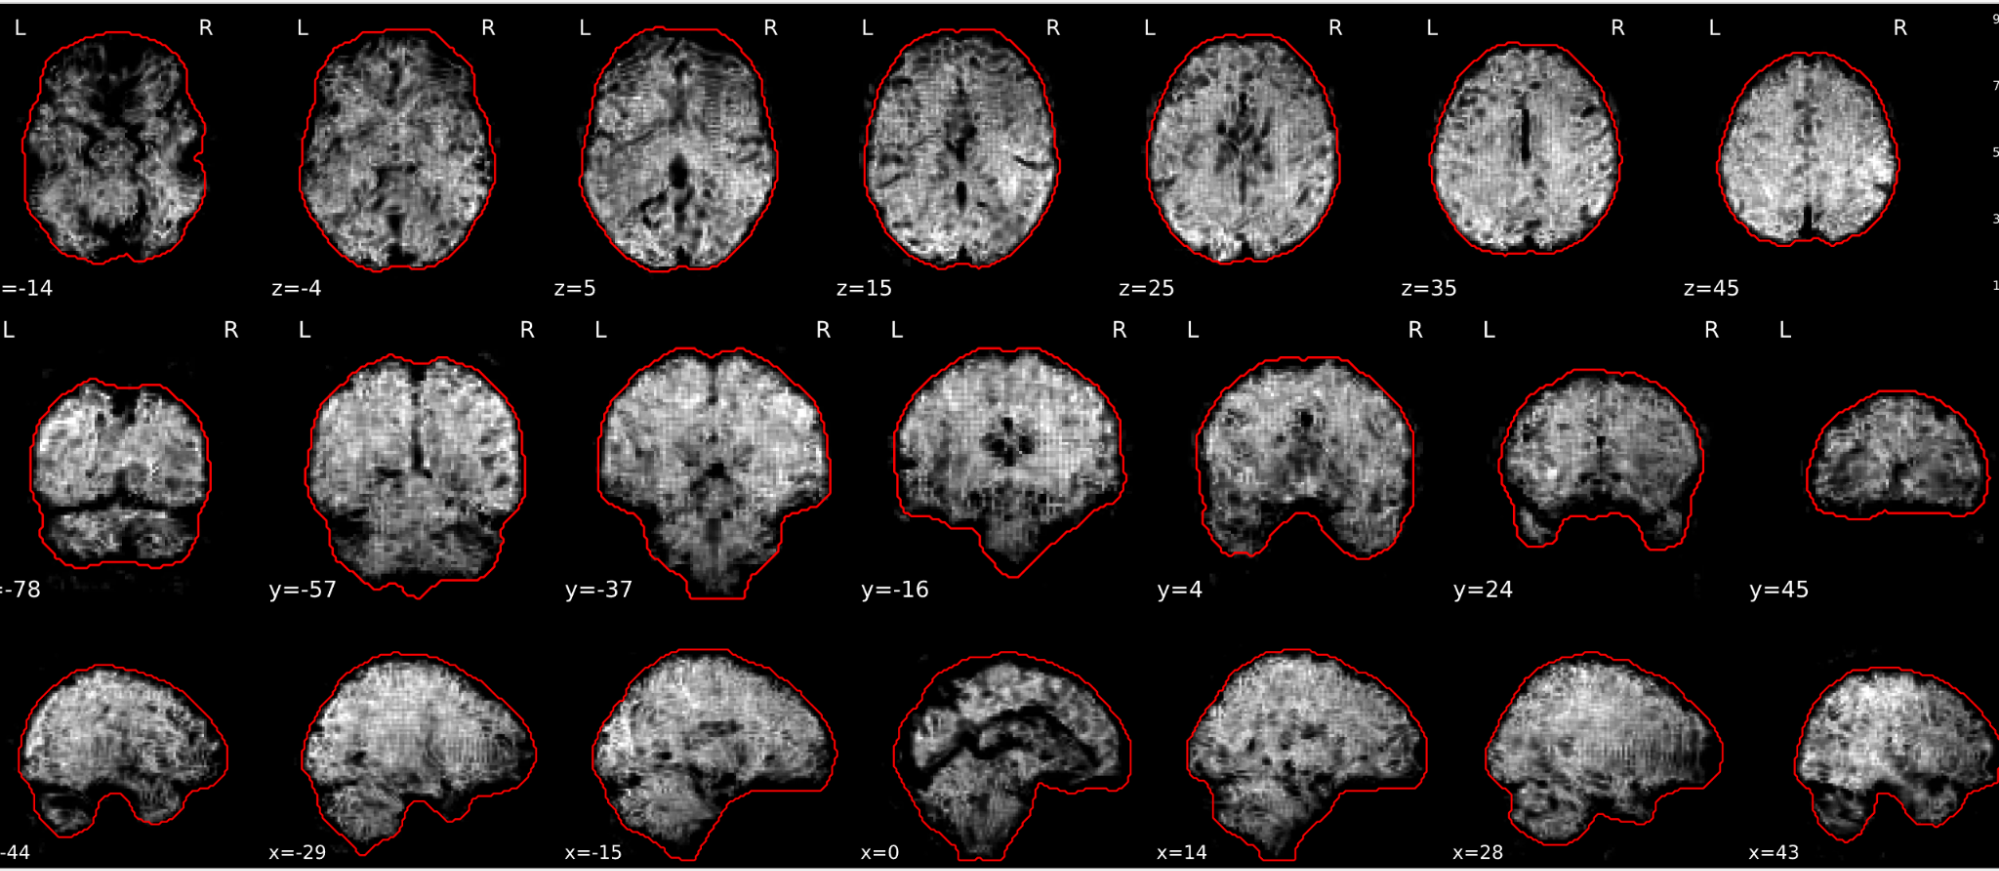

EPI tSNR

In the signal to noise ratio images of the resting state image the desired signal is compared to the amount of background noise. It is important to check all the views (sagittal, coronal, axial) because some artefacts (e.g., stripes) may be evident only in one particular view.

Example of a good subject

- Signal to noise is symmetrically distributed and there is no signal distortion

Example of a bad subject

- Asymmetry

- Potential signal distortion (might represent an artefact)

- Signal drop-out

- Stripes artefact

Clear large artefact (e.g., zebra stripes in example 1) are worth the exclusion of the subject. If you are unsure, check the other quality metrics for that subject to decide whether they should be excluded.

Summary

| good | bad |

|---|---|

| Symmetrical distribution of noise and signal | Asymmetry |

| No disruptions of the signal (no “black patches”) |

Potential signal disruptions (could be related to artefacts) |

| No stripes (sign of high motion) |

Signal drop |

| Stripe artefacts (“zebra” stripes due to motion) |